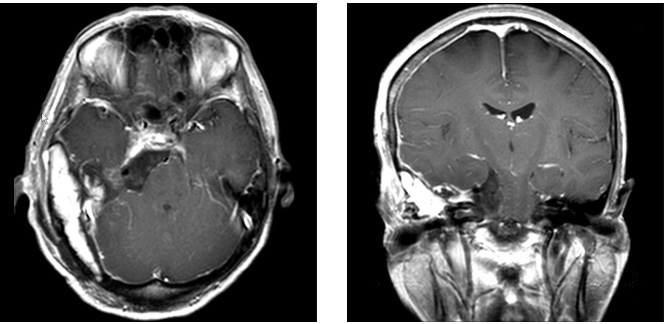

症例4

症例4は58歳。顔面の違和感で発見された小脳橋角部、テント髄膜腫である。三叉神経や外転神経、滑車神経などを巻き込む腫瘍。脳幹圧迫も強く症状は軽微であったが、腫瘍摘出を行った。後方複合錐体アプローチで一期的に神経を温存して腫瘍を摘出した。一時的に滑車神経麻痺による下方を見た時の副視が出現したが、改善している。

術前MRI 右側の脳神経を巻き込む腫瘍

神経を温存し腫瘍摘出